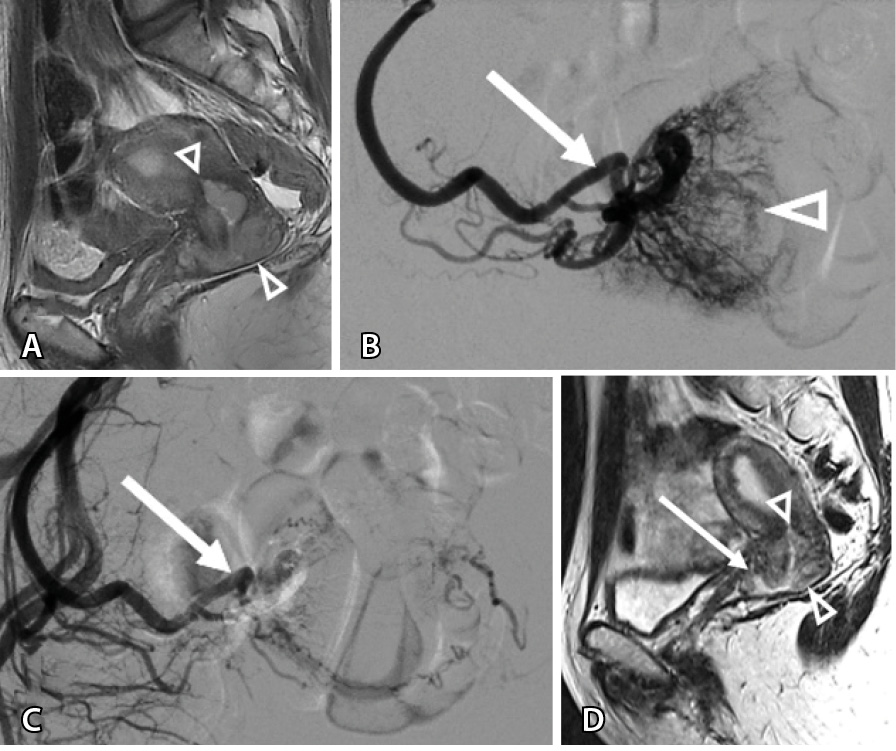

Вместе с тем изменения, происходящие внутри опухоли, влияли на тактику ведения пациенток. Так, за счет уменьшения толщины опухолевой массы в 17% всех случаев (n = 17) формировались участки истончения стенки органа до 1,5–2 мм (рис. 2), что потребовало коррекции сроков хирургического лечения.

Рис. 2. Женщина 31 года, первичный рак шейки матки: А – магнитно-резонансная томография в сагиттальной проекции: опухоль с инфильтративным ростом, вовлекающая шейку матки, нижнюю половину тела матки, передний свод влагалища (треугольные стрелки); Б – этап трансартериальной химиоэмболизации: на ангиограмме определяется сеть опухолевых афферентов (треугольная стрелка), отходящих от маточной артерии (стрелка); В – результат эмболизации: опухолевые афференты не контрастируются, проходимость маточной артерии сохранена (стрелка); Г – магнитно-резонансная томография в сагиттальной проекции через 14 дней: уменьшение протяженности и толщины опухоли (треугольные стрелки) с резким истончением стенки переднего свода влагалища (стрелка)